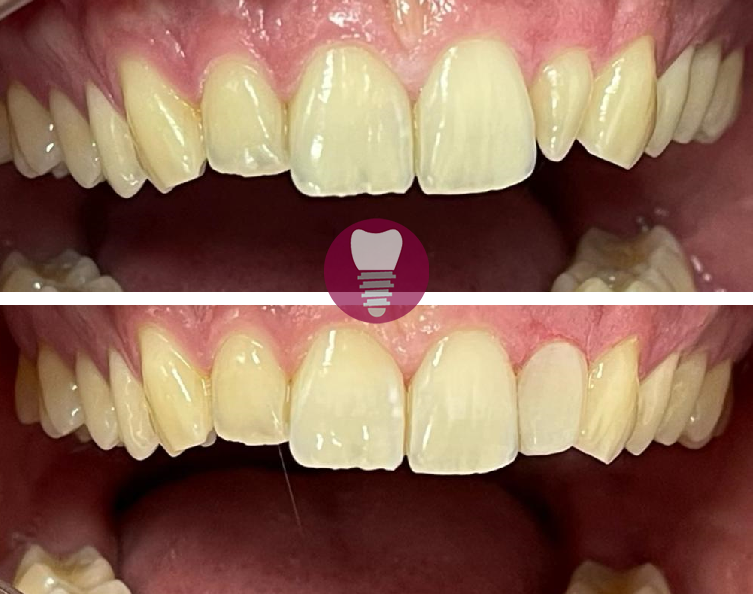

Las carillas dentales son láminas finas de material cerámico o resina compuesta que se adhieren a la superficie de los dientes para mejorar su apariencia. Este tratamiento es ideal para corregir imperfecciones como manchas, fracturas, microdoncia o caries visibles, devolviendo a los dientes un aspecto estético y natural. Las carillas se diseñan a medida, adaptándose al tamaño, color y forma de cada diente para lograr un resultado armonioso y duradero.

1.1 – Carillas de laterales